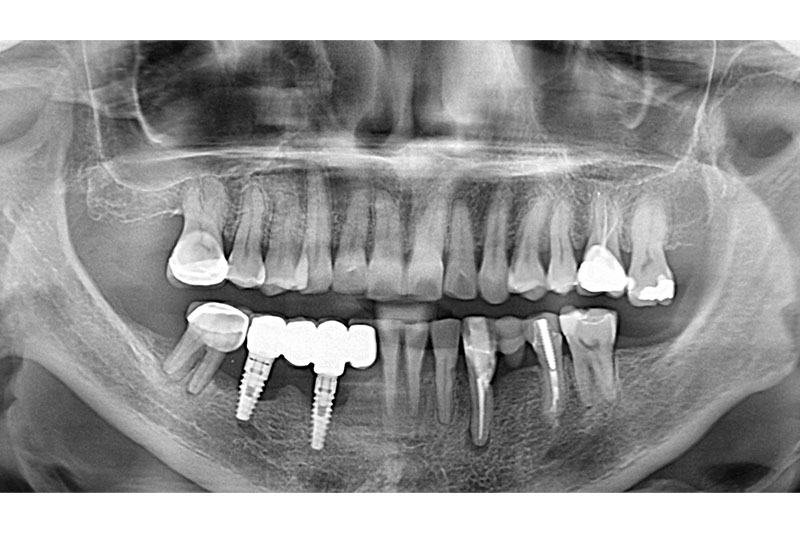

術後16年の口腔内とレントゲン写真

上下顎インプラント埋入後レントゲン

インプラントオーバーデンチャー装着時口腔内とレントゲン

インプラントオーバーデンチャー装着5年後の口腔内とレントゲン